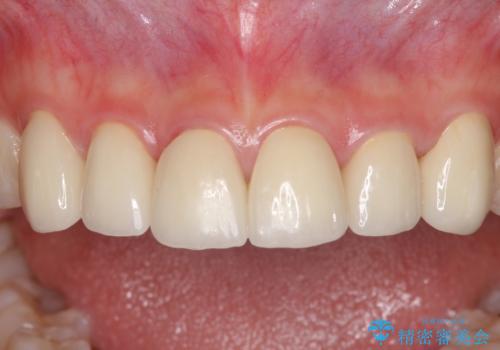

普段は海外在住であり、出産のための一時帰国を利用して短期集中治療を行いました。

自身の出産で大変な時期にもかかわらず、スケジュール通りに通院いただき、望まれたとおりの口元に仕上げることができました。